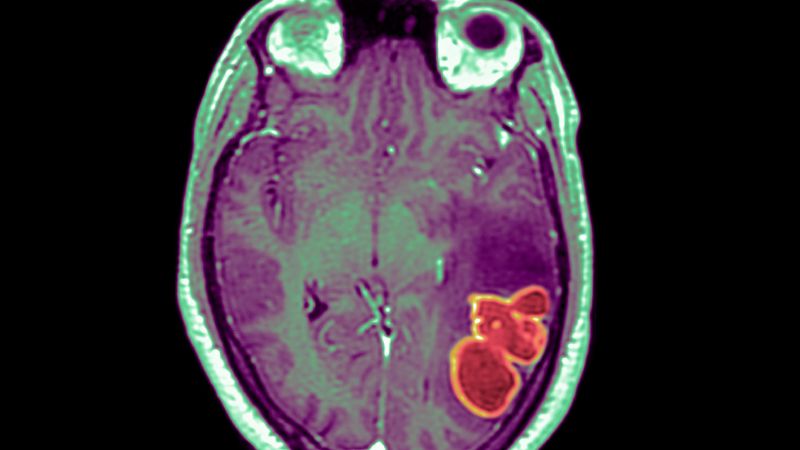

Cases of brain abscesses in American children have surged to new heights following the easing of pandemic restrictions, according to reports from the CDC. These abscesses, which are relatively rare but dangerous, are typically caused by bacteria or fungi entering the brain through respiratory infections such as COVID-19, the flu, or sinusitis. The CDC emphasizes the importance of children staying up-to-date with their vaccinations to prevent these infections. While cases have fallen since a peak in December 2022, they remain above the baseline maximum, indicating the need for continued monitoring and vigilance.